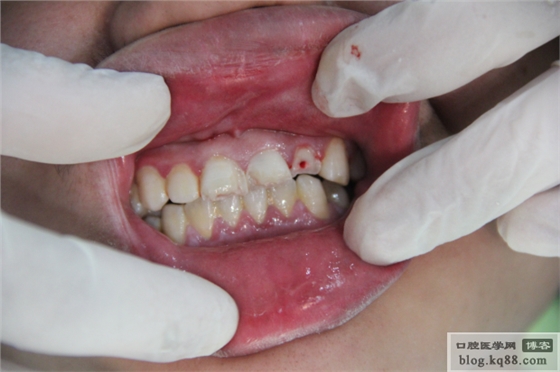

哈哈,不錯吧。功能很強(qiáng)大的,帶根管測量功能的根管治療儀。下面來看一列病例吧。患者男,22歲,昨晚喝醉酒后騎摩托摔倒。門牙碰斷。

片子顯示牙根沒有折斷。右上2已漏髓,兩個1也有出血點(diǎn)。建議根管治療,待烤瓷修復(fù)。局麻下開髓,測量根管長度,機(jī)括至大錐度F2.次氯酸鈉加鹽水大量沖洗。預(yù)備完成,看看試尖片。